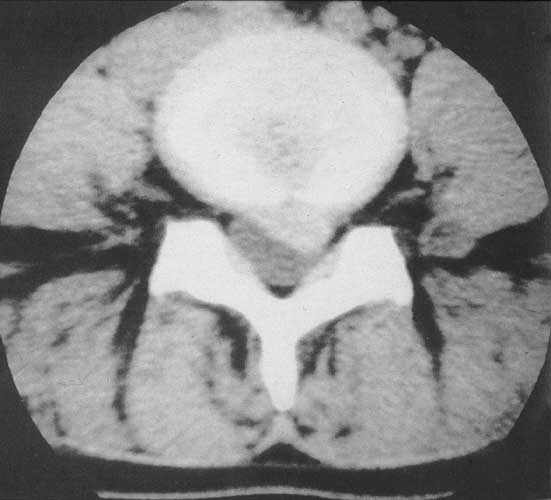

Abb: links, im Computertomogramm